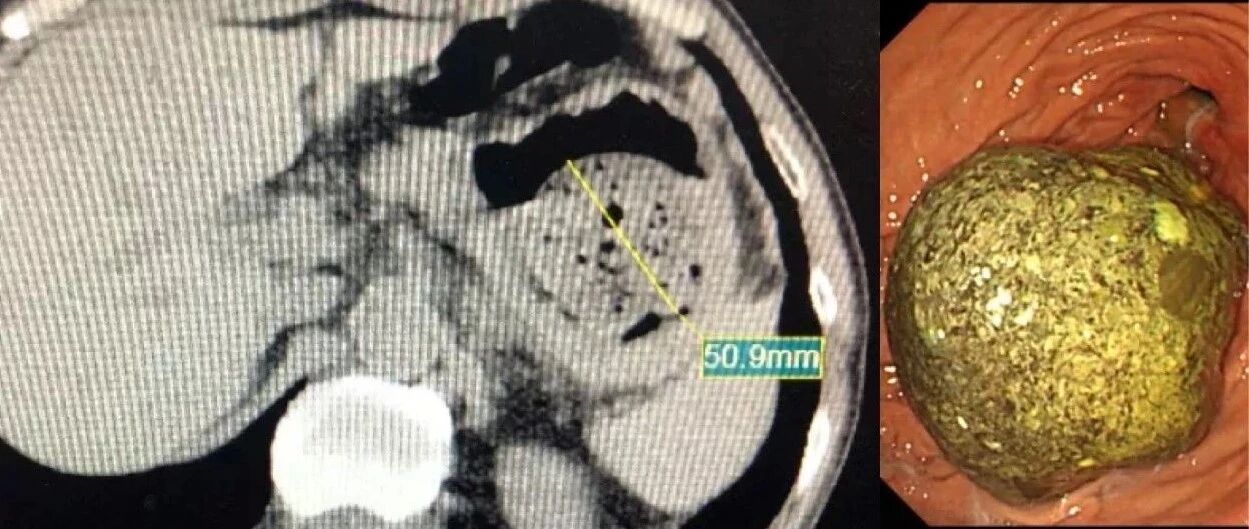

浙江男子爱吃一种水果,体内长出“金色巨石”!医生20多次没取完……

来源:浙江在线健康网

吃完这水果,浙江男子体内长出金色巨石!突然卡住了...

来源:杭州日报